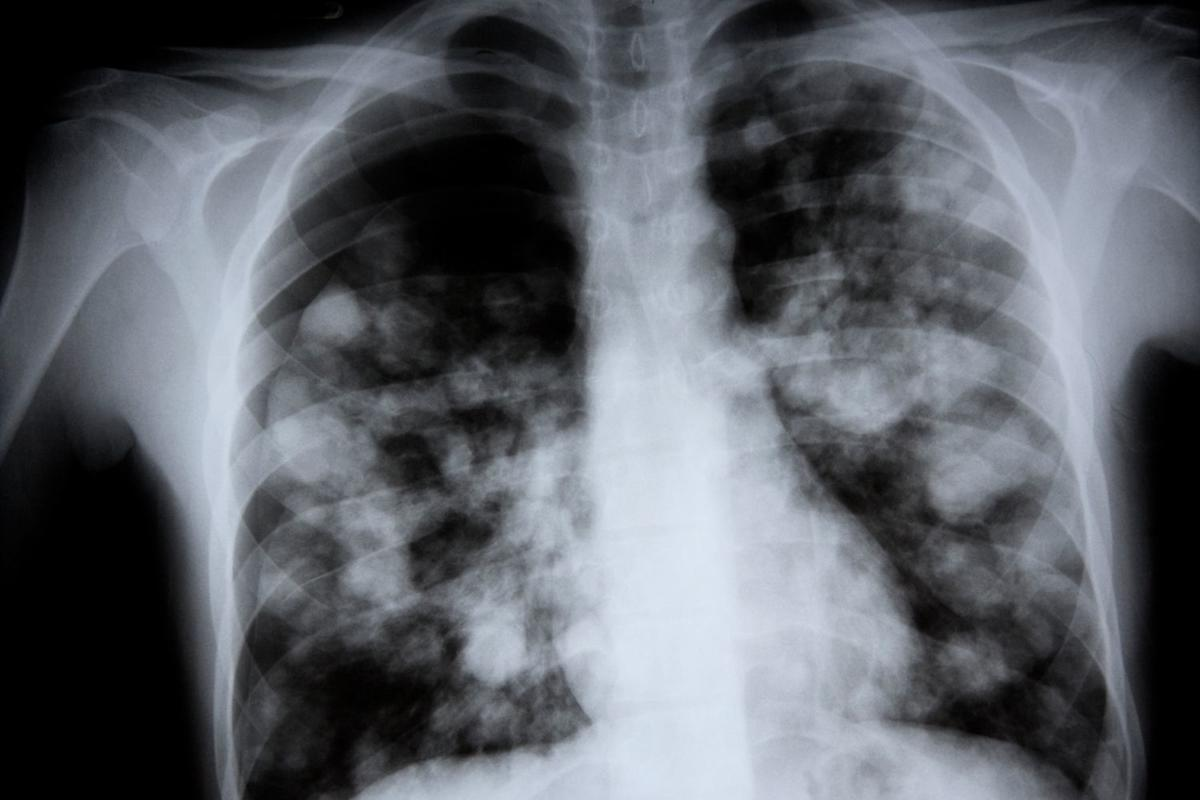

Chest X-rays and CT Scans

Imaging tests like chest X-rays and CT scans are important for seeing the lungs. Chest X-rays can show hyperinflated lungs by showing flattened diaphragms and increased lung volumes. CT scans give more detailed pictures. They help see how much damage there is and rule out other problems.